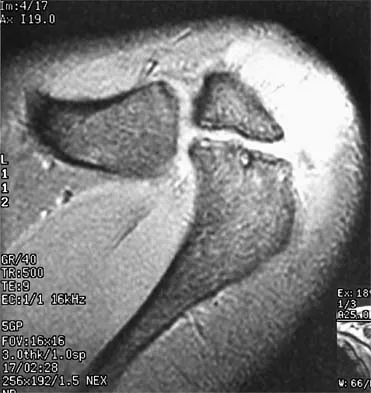

A 47-year-old male tennis player has pain in his nondominant shoulder that has failed to respond to 4 months of nonsurgical management. Examination reveals acromial tenderness and pain at the supraspinatus tendon insertion. He has a positive impingement sign, pain on forward elevation, and minimal cuff weakness. The MRI scans are shown in Figures 30a and 30b. To completely resolve his symptoms, treatment should consist of

The MRI scans show a mesoacromion with tendonopathy of the supraspinatus. The history and physical findings indicate that the patient has a symptomatic os acromiale. Simple excision of the unstable os acromiale has not yielded consistently good results. Meticulous internal fixation using tension banding with cannulated screws and autologous bone grafting has shown good results for this problem. Hutchinson MR, Veenstra MA: Arthroscopic decompression of shoulder impingement secondary to os acromiale. Arthroscopy 1993;9:28-32.

- Warner JJ, Beim GM, Higgins L: The treatment of symptomatic os acromiale. J Bone Joint Surg Am 1998;80:1320-1326.